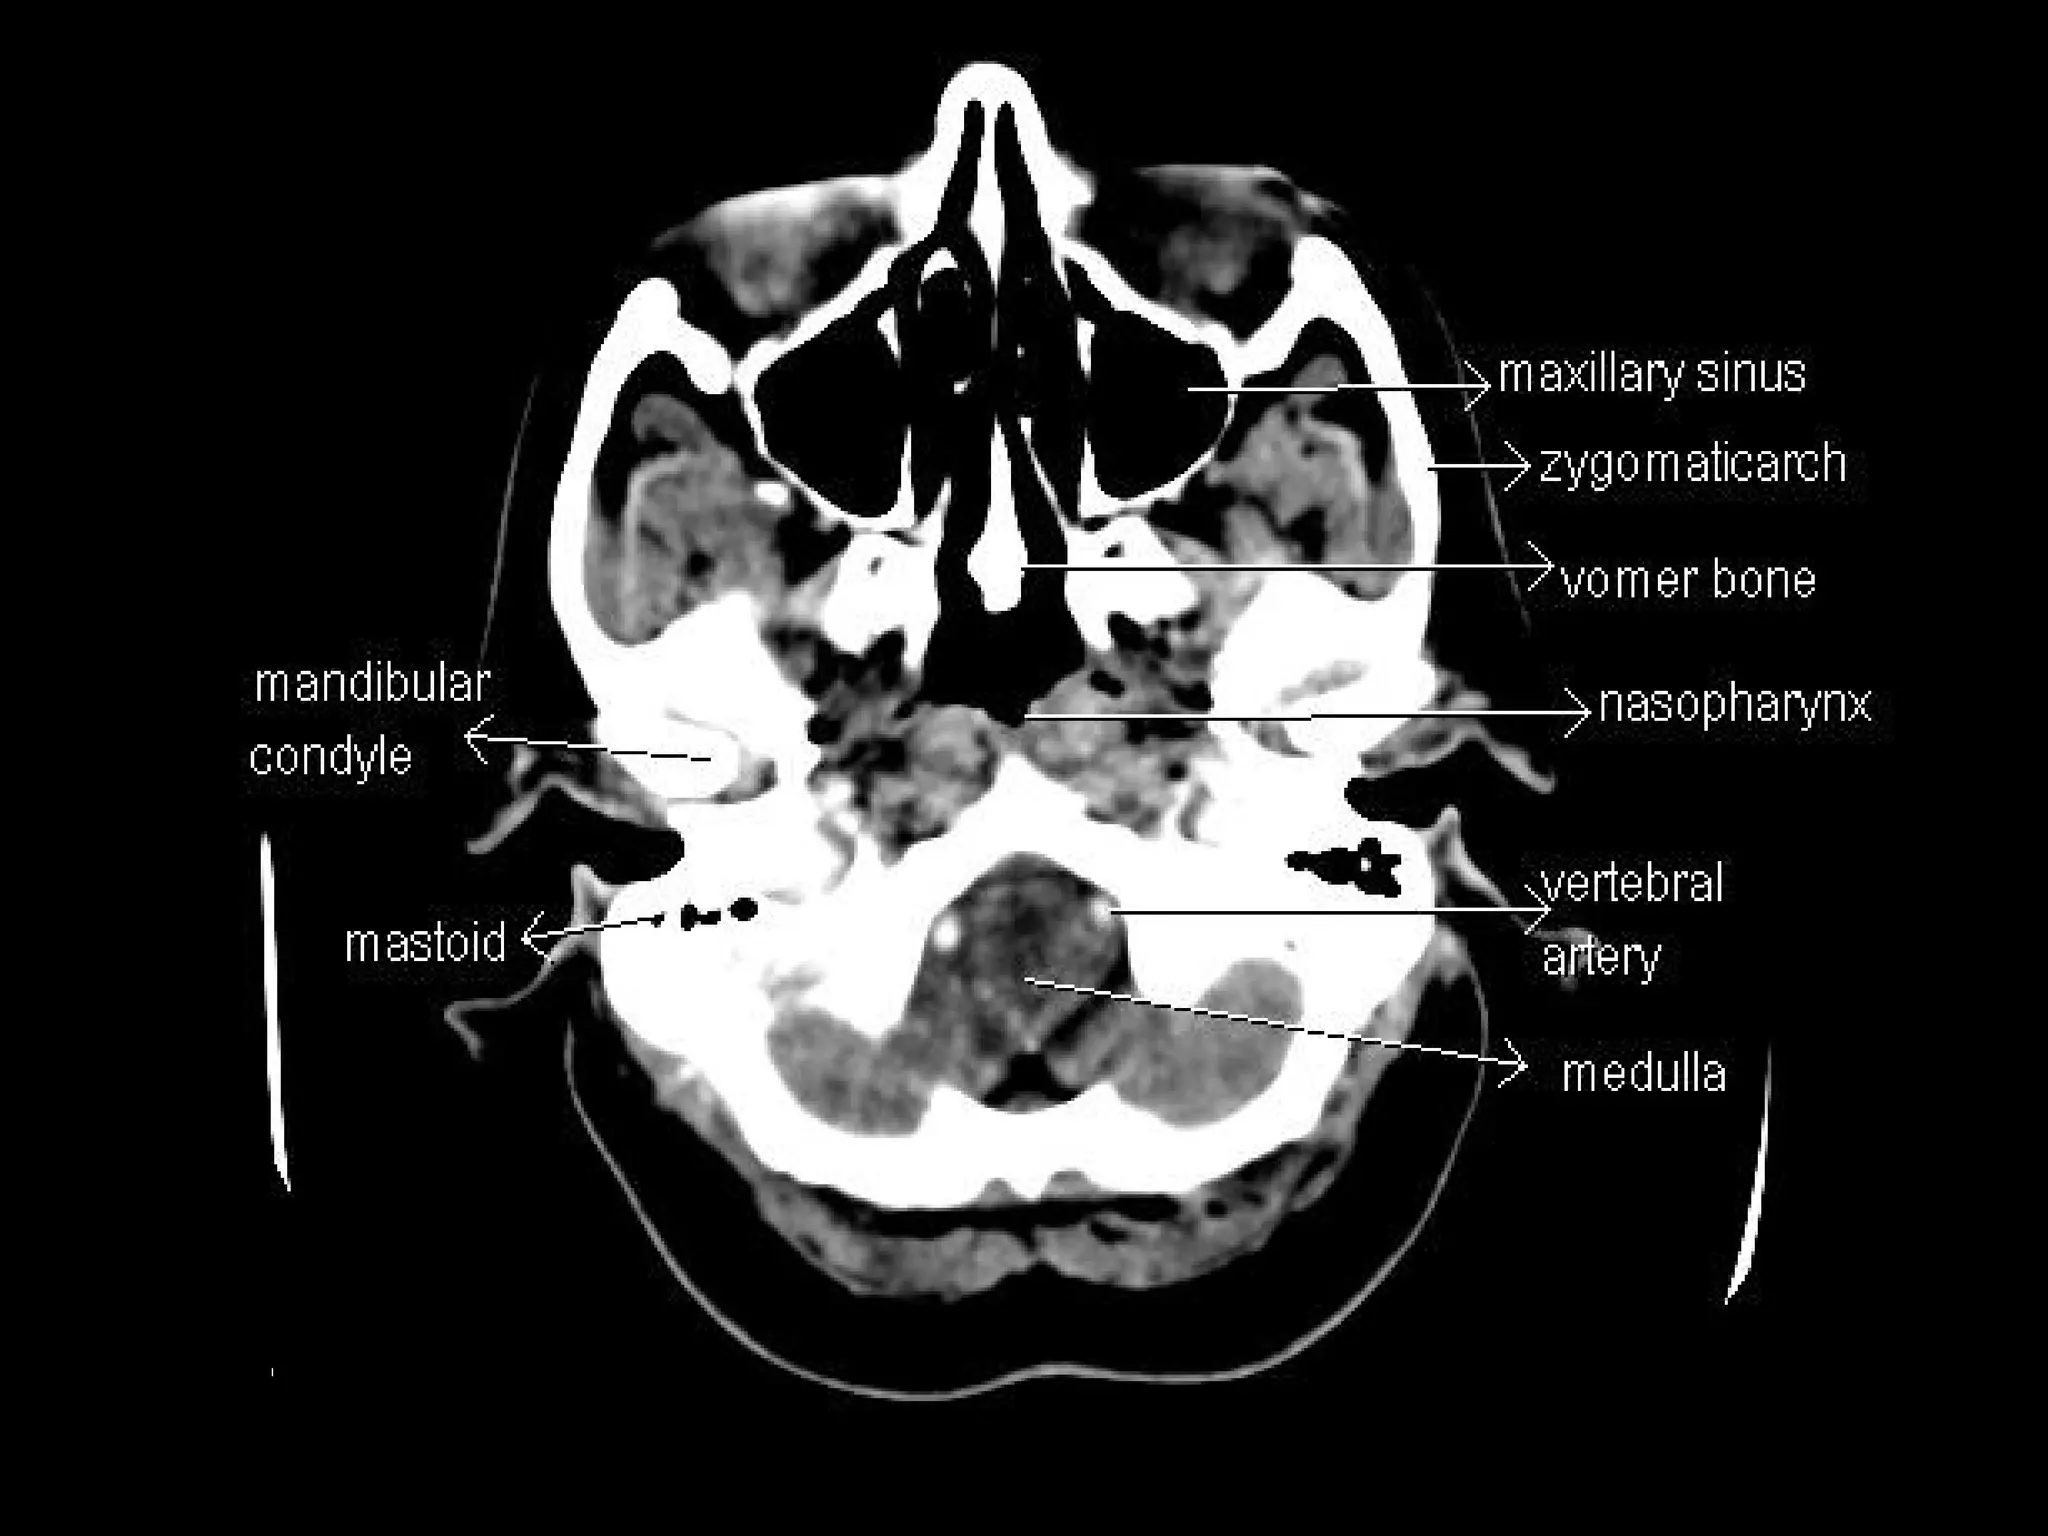

Radiographers are medical professionals who perform diagnostic imaging examinations and procedures to help physicians diagnose and treat diseases. They work under the supervision of radiologists to operate X-ray, CT, MRI, ultrasound and other medical imaging equipment and must have a strong understanding of human anatomy and pathology. Radiographers are responsible for correctly positioning patients, ensuring proper imaging techniques are used, and evaluating the quality of the resulting images.